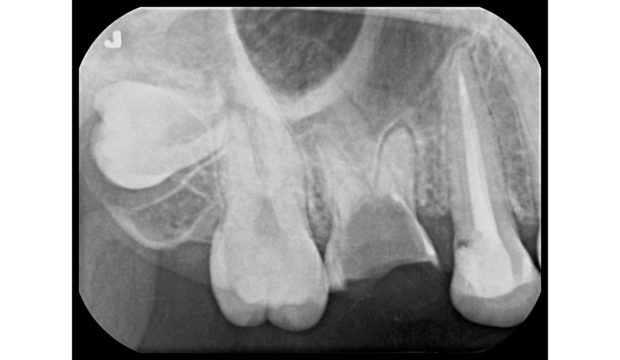

今回のケースは左下奥歯の根が割れていたので残すことが難しく、左下の親知らずを抜歯していなかった為、左下6番へ移植することとなりました。

まず始めに、CT(3次元レントゲン)を利用して抜歯予定の歯の大きさを測定します。

親知らずの大きさも測定し、抜歯予定部位に入る大きさなのかの診断をします。

この際に親知らずが少し大きいようなら、抜歯部位の周りの骨を少し削り、親知らずが入るように調整をしなければなりません。

なので、移植する際はCT撮影(3次元レントゲン)が必須です。

上記の写真が抜歯直後の親知らずです。

親知らずを抜歯する際は今後も使用する歯になるので、根が折れたり、割れたりしないように、慎重に抜歯します。